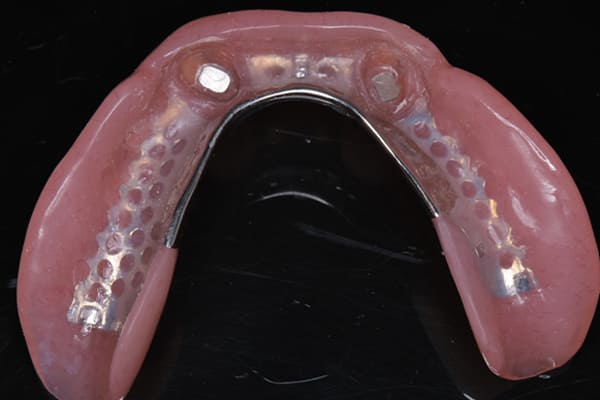

- 上顎精密金属床総入れ歯

- 下顎精密金属床総入れ歯

- 磁性アタッチメント(白金加金) 3歯

下の総入れ歯は外れやすいため大きな虫歯はありましたが、虫歯治療を行い、根のみ残せた2本の歯に磁石を利用することで歌われた際も外れない入れ歯の設計としました。

下顎は舌があるため、上顎と比較すると総入れ歯の場合、外れやすい傾向があります。患者様はまだお若く、お肉がお好きだったとのこと、またお歌もご趣味とのことで、ご相談の上、なるべく外れない設計としました。

磁石を用いた入れ歯の設計により上下の入れ歯は、お食事やお歌を歌われ大きなお口を開けても外れない状態が可能になりました。